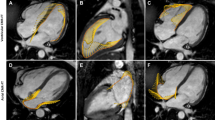

Our study subjects (n = 164) consisted of four groups: normal controls (n = 32), grade I DD (n = 69), grade II DD (n = 42), and grade III DD (n = 21). On average, patients with DD were 60 ± 14 years old and about half (N = 63) had advanced DD (grades II or III). Normal LVEF (> 50%) was present in 18 (14%) patients. Baseline characteristics of each DD grade are displayed in Table 1. Examples of phasic LA strains are shown in Fig. 1 where graded decreases of LA strains are shown from normal to grade 1, II and III diastolic dysfunction. Phasic LA strains and LAEF were progressively lower with increasing severity of DD (p < 0.001) (Fig. 2A–C, F; Table 2). Similarly, LV longitudinal strain was also progressively lower (Fig. 2G). Conversely, LAVmin and LAVmax were significantly higher with increasing severity of DD (p < 0.001) (Fig. 2D, E).

The graded change of left atrial reservoir strain (A), left atrial conduit strain (B), left atrial booster pump strain (C), left atrial minimum volume (D), left atrial maximum volume (E), left atrial emptying fraction (F), and left ventricular global longitudinal strain (G) in relation to the severity of left ventricular diastolic dysfunction. ANOVA with post-hoc Dunnett’s test yielded statistically significant differences between the means (p < 0.05) in each panel.